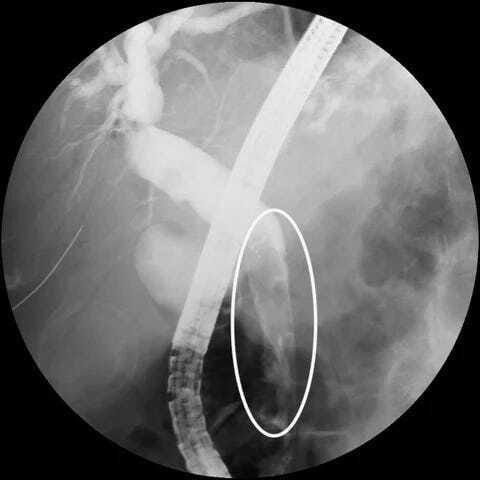

ERCP: Multiple irregular defects in biliary tree

Treatment: Biliary sphincterotomy, blood clot extraction, plastic stent insertion (removed after 4 weeks)